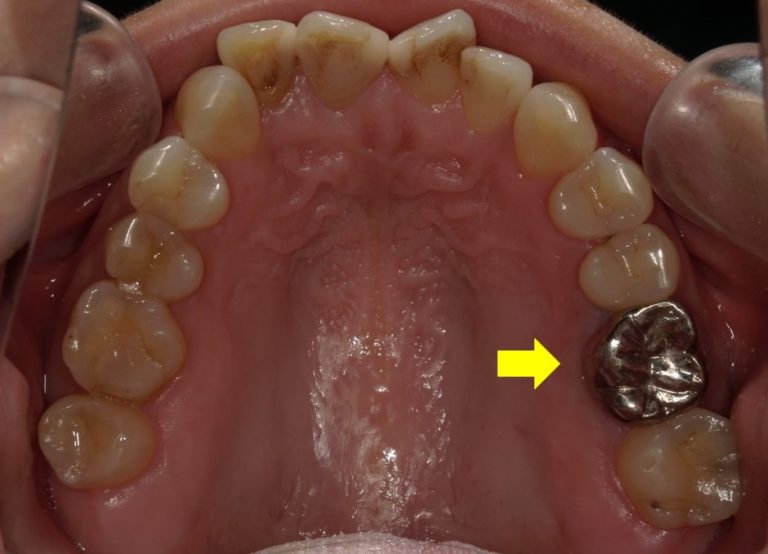

一部条件はありますが、いわゆる4番、5番、6番の歯については白い被せ物も可能となってきました。